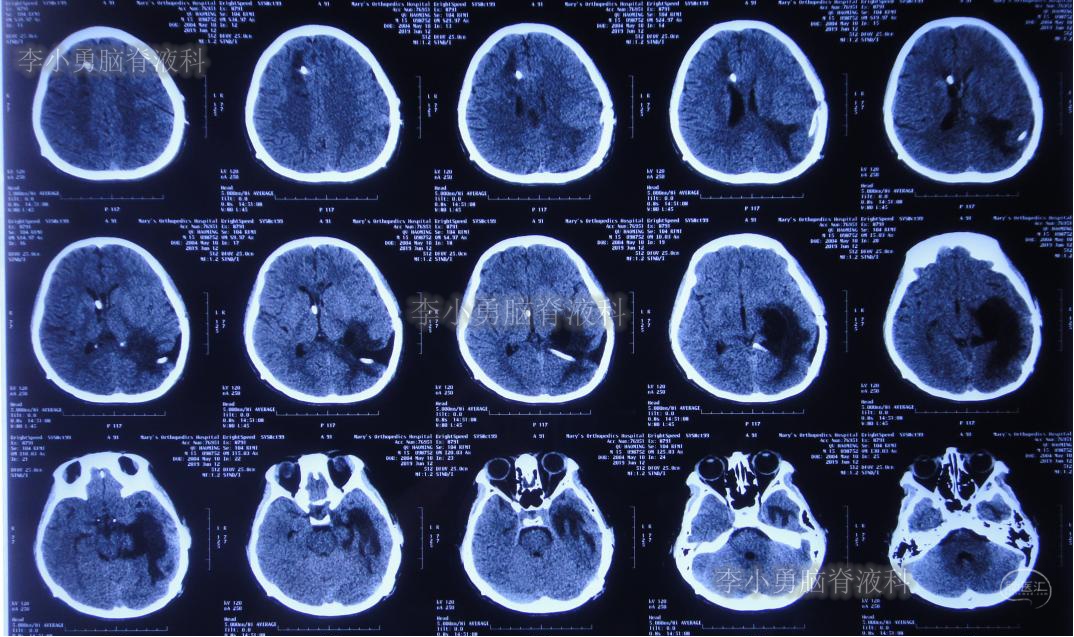

入院当日行头颅CT(图-10):脑室内“动脉瘤切除术”后改变,术区可见引流管影,脑室扩大。

图-10:2019年5月7日头颅CT:引流术后,脑室扩大

入院次日即2019年5月8日,进行了右侧脑室外引流术,并保留原来脑室外引流管(注:脑室内有两根管)。术后常规复查头颅CT(图-11)。

图-11:2019年5月9日头颅CT:引流出淡黄色脑脊液

但是患者逐渐开始出现头部不适,轻度头痛,且近期记忆力很差。右侧脑室外引流术后25天即2019年6月3日,再次复查头颅CT(图-15):右侧颞角再次扩大并周边水肿明显,术区水肿。

图-15:2019年6月3日头颅CT:左侧颞角扩大并周围水肿

图-16:2019年6月12日头颅CT:左侧颞角进一步扩大并水肿加重

图-17:2019年6月13日头颅CT:拔除原术区引流管

拔管后患者头痛逐渐加重,记忆力逐渐减退。于拔管后11天即2019年6月24日复查头颅CT(图-18):左侧颞角积水加重。

图-18:2019年6月24日头颅CT:左侧颞角扩大加重

次日即2019年6月25日,进行了左侧颞角外引流术;术后次日复查头颅CT(图-19):左颞角引流管位置良好。

图-19:2019年6月26日头颅CT:左侧颞角引流术后

左侧颞角引流术后20天即2019年7月17日,复查头颅CT(图-21):左侧颞角积水消失,水肿消退;患者记忆力也逐渐好转。

图-21:2019年7月17日头颅CT:左侧颞角积水消失,水肿消退

左侧颞角引流术后33天即2019年8月1日,给予试夹闭右侧脑室外引流管,闭管前复查头颅CT(图-22)。

图-22:2019年8月1日夹闭前复查头颅CT

闭管40天后即2019年9月9日复查头颅CT(图-23):脑室仍无扩大。给予拔除右侧脑室外引流管并行左侧颞角-腹腔分流术。

图-23:2019年9月9日头颅CT:拔除右侧脑室外引流管后复查